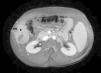

We present the case of a 35-year-old man with a history of chronic hepatitis C virus infection with progression to cirrhosis. He was subsequently diagnosed with hepatocellular carcinoma, which was treated with concomitant radiofrequency ablation and percutaneous ethanol injections. A year after treatment, the patient presented with a subcutaneous nodule in the right costal region (Figure 1). The site of the lesion appeared to coincide with that of the radiofrequency needle tract. Computed tomography showed a large lesion consistent with progression of the hepatocellular carcinoma on the right abdominal wall, in addition to multiple intrahepatic metastatic masses (Figure 2). Skin biopsy confirmed that the cutaneous lesion was a metastasis from the hepatocellular carcinoma (Figure 3). Surgical treatment and chemoembolization were ruled out because of the size of the lesion. The patient was administered chemotherapy (sorafenib) and radiation therapy in the scar area, but died 5 months after diagnosis of the cutaneous metastasis.